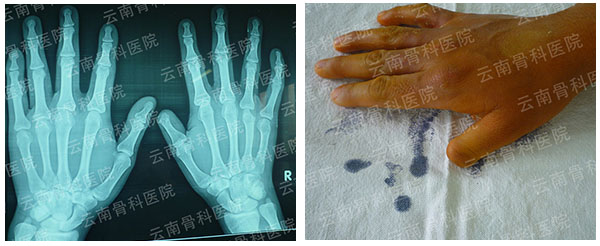

拇指Ⅳ度再造